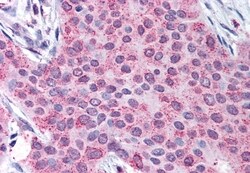

Percent identity with other species by BLAST analysis: Human, Gorilla, Gibbon, Monkey (100%); Marmoset, Dog, Bovine, Elephant (94%); Panda, Horse, Rabbit, Pig (88%); Mouse, Rat, Sheep (82%). For IHC(P), use heat induced antigen retrieval in pH 6.0 citrate buffer. After incubation with the primary antibody, slides were incubated with biotinylated secondary antibody, followed by alkaline phosphatase-streptavidin and chromogen.

| Immunohistochemistry (Paraffin) | |